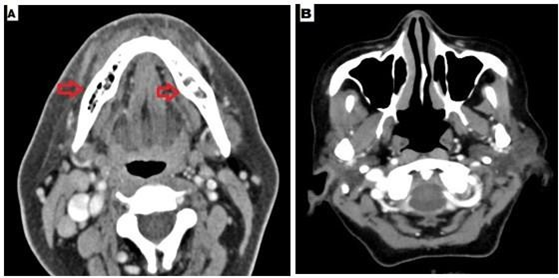

Sinus endoscopy did not reveal any mucosal disease, CT image of the sinus was also normal. HbA1C was 9.7%. Z-orthopantomogram showed bilateral mandibular erosions (Figure 5). CT showed bilateral mandibular osteomyelitis (Figure 6). Debridement was performed and histopathology revealed broad aseptate and pauciseptate fungal hyphae with obtuse angle branching. There was significant bony and angioinvasion; a characteristic feature of invasive mucormycosis. Fungal culture was negative. She was started on injection lipid emulsion amphotericin b and was continued for 2 weeks. She responded well and was switched to tablet posaconazole after 2 weeks. Serum trough level was performed after 7 days and was found to be 1483 ng/ml.

Figure 6 A- CT mandible revealed bilateral mandibular osteomyelitis with cortical expansion, B- CT paranasal sinuses – normal.